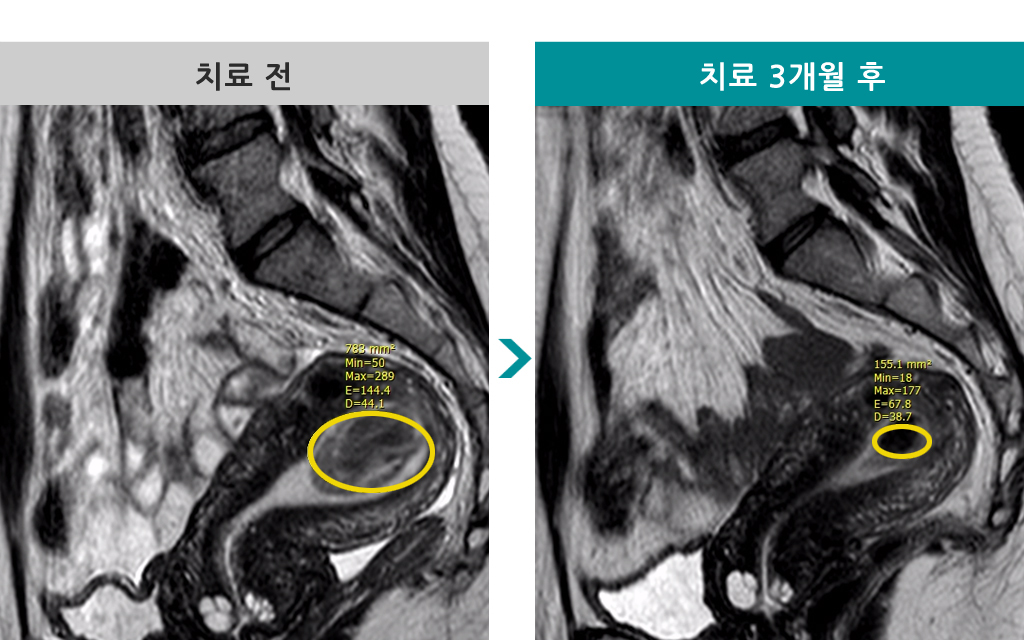

43세 [자궁근종 색전술] 전후 MRI사진 비교